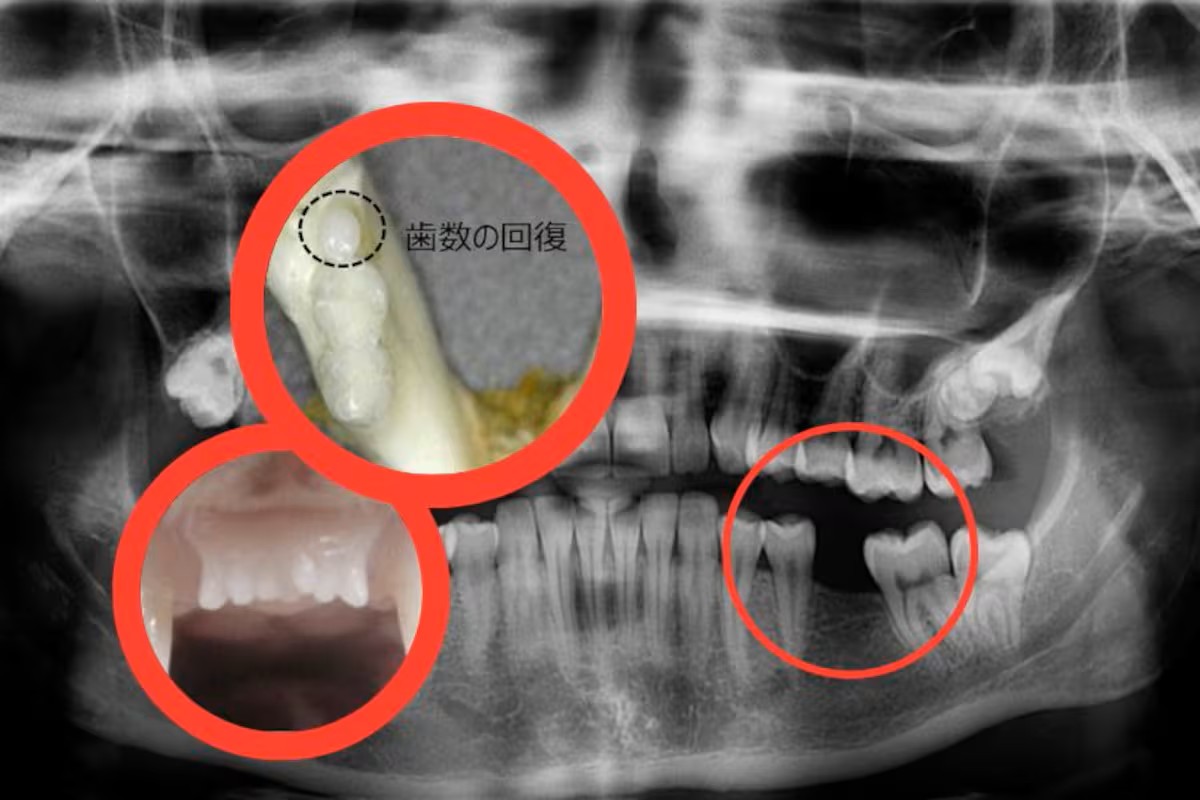

Japón se coloca a la vanguardia de la odontología regenerativa con el inicio de ensayos clínicos en humanos de un medicamento experimental que promete hacer crecer un tercer juego de dientes.

El fármaco, identificado como TRG-035, fue desarrollado por el doctor Katsu Takahashi y su equipo en la Universidad de Kioto, y actúa neutralizando una proteína llamada USAG-1, la cual bloquea de manera natural el crecimiento de nuevas piezas dentales.

El objetivo inicial es confirmar la seguridad del tratamiento en humanos, tras los resultados positivos obtenidos en ratones y hurones, que lograron desarrollar dientes nuevos y funcionales sin efectos secundarios.

De confirmarse su eficacia, la segunda fase de estudios se enfocará en niños con agenesia dental congénita, una condición poco común que impide el desarrollo de múltiples piezas. Expertos internacionales califican el avance como “emocionante”, aunque insisten en que aún falta un largo camino de pruebas y regulaciones antes de su uso generalizado.